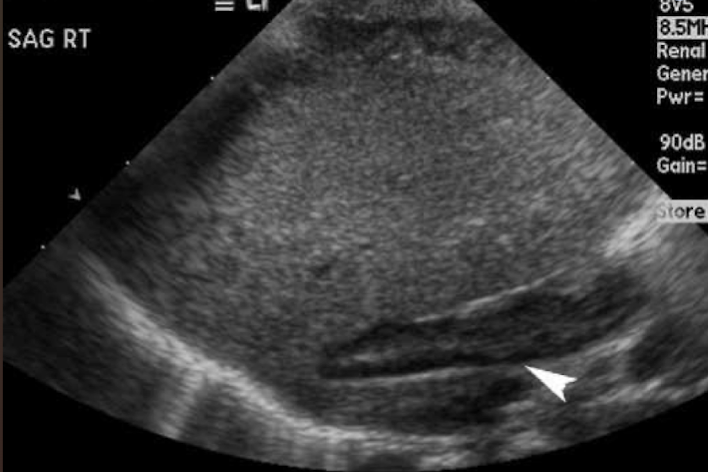

adrenal glands

endocrine organ

could possibly be seen with US in infants and young children

consists of an independently functioning cortex and medulla

supplied by suprarenal arteries

drained by suprarenal vein